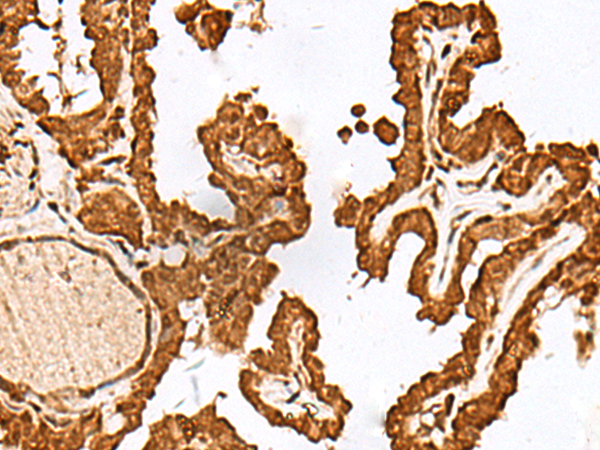

IHC positive control:

Human esophagus cancer and Human thyroid cancer

IHC Recommend dilution:

40-200